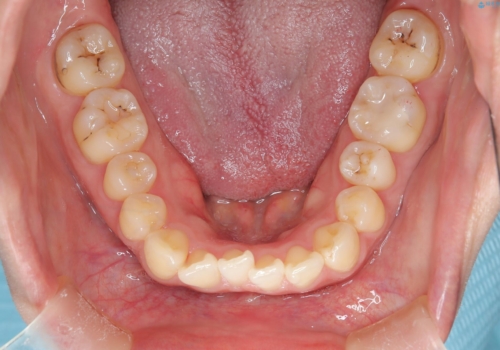

- 口元の突出感、歯のがたつきを主訴に来院された患者様です。非抜歯にて口元を下げるような治療計画を立案しました。非常に治療に対して真面目で協力的な患者様で、一緒に理想形を相談しながら治療を進めました。矯正前には、虫歯治療や親知らず抜歯を行っています。噛みしめ癖が強く、終盤は奥歯の噛み合わせのためにゴム掛けにご協力いただきました。